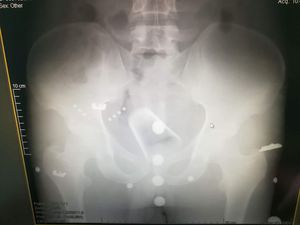

This case came to ER with glass in his pelvic cavity which enters his pelvis through the anal canal๐ณ๐ฑ๐

I would have to be professional and not laugh when patients would tell me they "fell" on whatever object that had been inserted๐๐๐